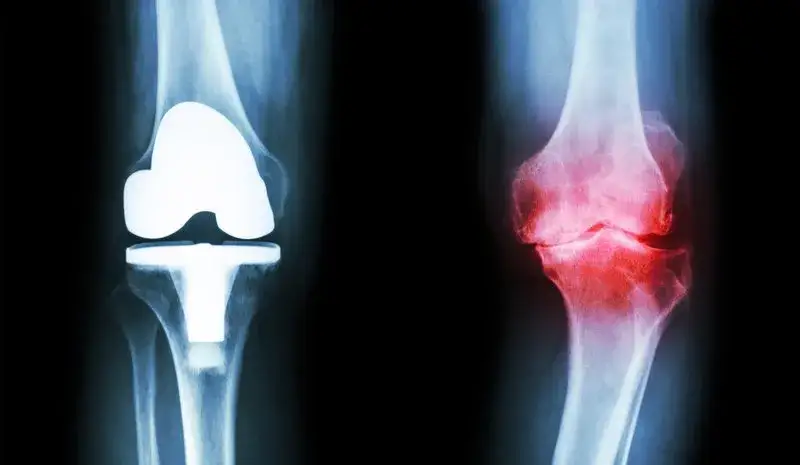

Do jakiego lekarza iść z zwyrodnieniem stawów w zaawansowanym stadium? Ortopeda staje się kluczowym specjalistą, gdy zmiany zwyrodnieniowe są znaczne i wymagają interwencji chirurgicznej. Jest on ekspertem w zakresie operacyjnego leczenia stawów.

Szczególnie ważna jest konsultacja ortopedyczna, gdy leczenie zachowawcze nie przynosi oczekiwanych rezultatów. Ortopeda ocenia wówczas możliwość wykonania zabiegu operacyjnego, takiego jak artroskopia czy endoprotezoplastyka.